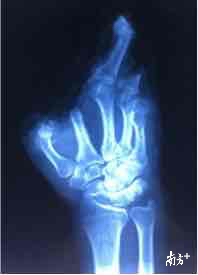

近日,深圳一名建筑工人在工地上意外受重伤,导致右手五指完全与手掌脱离,经过深圳市第二人民医院手足外科团队全体协作,连续昼夜奋战18个小时,终于把五指全部再植成功。

就这样,手足外科的全体医生团结协作,昼夜奋战近18个小时,终于在第二天早上8点成功完成五指撕脱离断的再植手术,患者右手完全离断的五个伤指在离体10多个小时后被全部原位接回。看着患者安全送出手术室,连续忙碌了整整一天一夜的医生们已经几近虚脱。